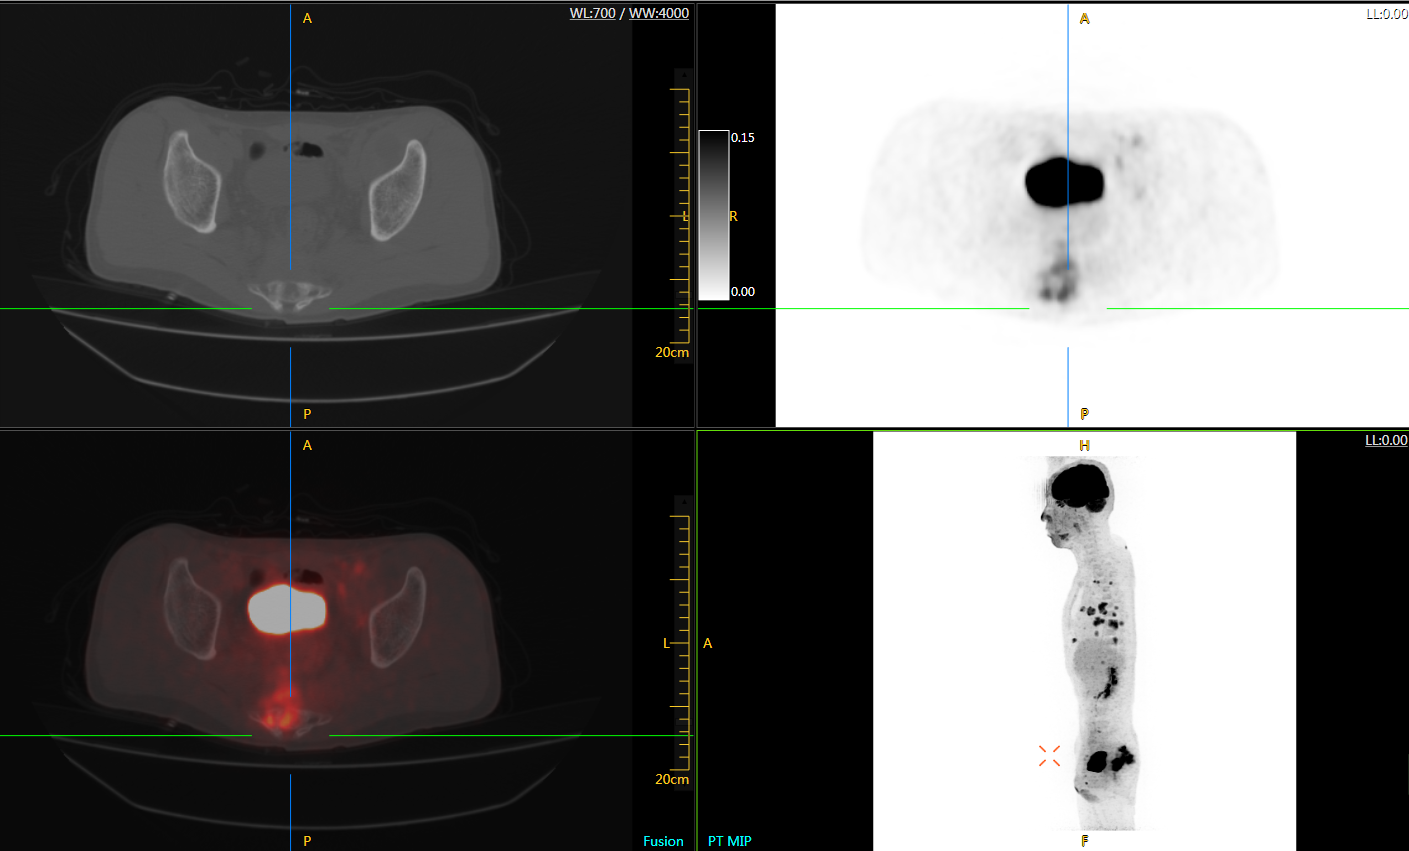

直腸癌

男,45歲,直腸癌術(shù)后9個月,發(fā)現(xiàn)肺占位

臨床診斷:直腸區(qū)術(shù)后改變,復發(fā)伴骶骨受累,雙肺多發(fā)轉(zhuǎn)移

肺癌轉(zhuǎn)移及復發(fā)

患者男性,66歲,七年前發(fā)現(xiàn)右肺肺癌,其間手術(shù)兩次,共切除兩個肺葉,復查;

診斷意見,回腸轉(zhuǎn)移,右肺殘留部復發(fā)